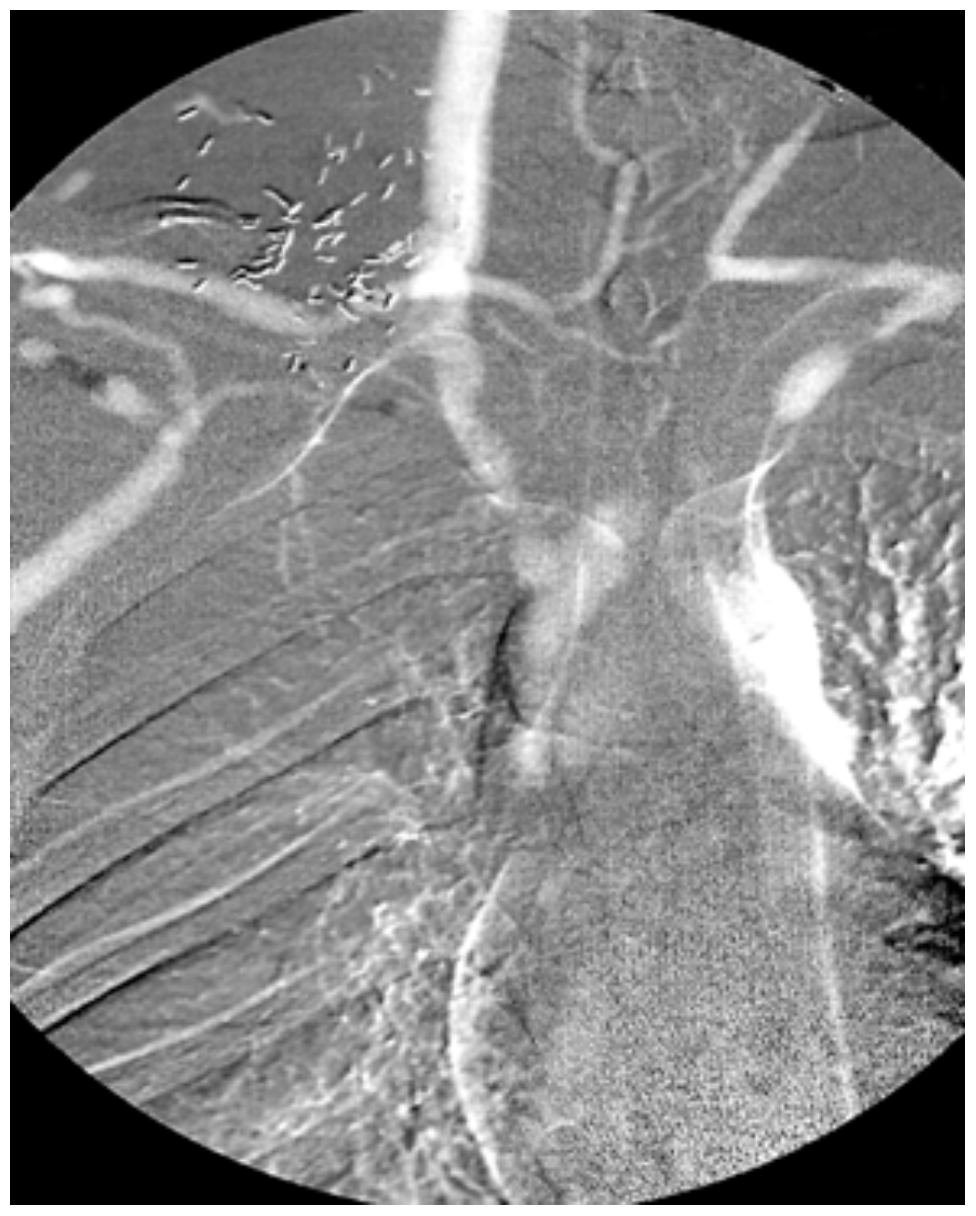

DSA (Pelvis) Radiology SUNY Upstate Medical University

DSA (Pelvis) Radiology SUNY Upstate Medical University Radiology Dsa digital subtraction angiography, or dsa, is a procedure that provides an image of the brain's blood vessels using contrast dye. digital subtraction angiography maintains an important role in a number of clinical applications, even with. digital subtraction angiography (dsa) is a fluoroscopic technique used extensively in interventional radiology for visualization of blood. digital subtraction angiography (dsa). Radiology Dsa.